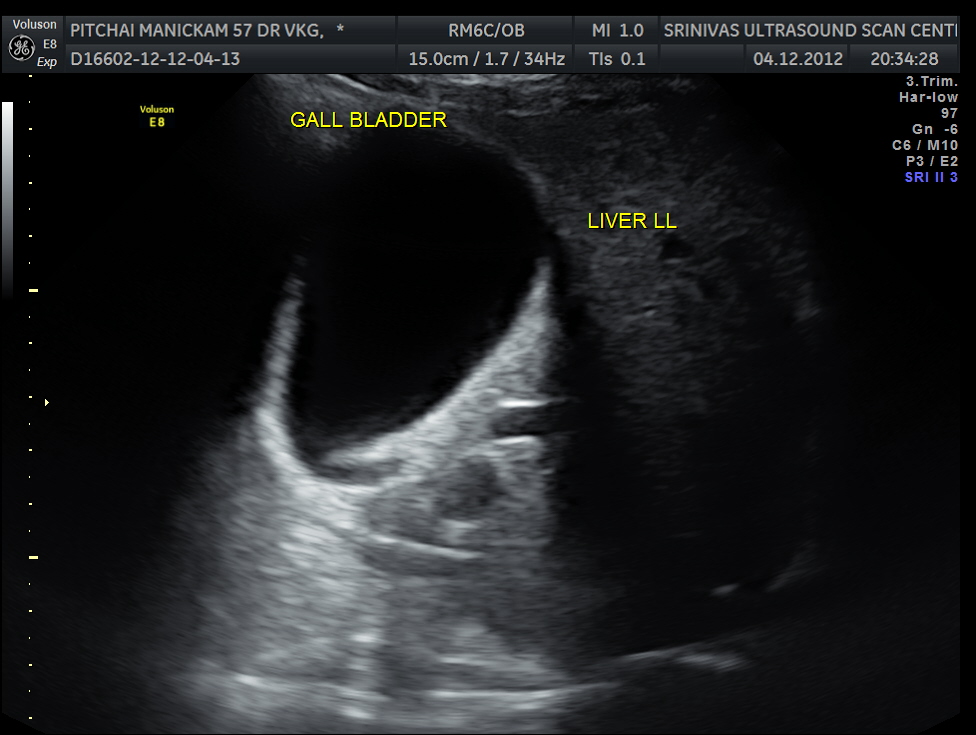

Liver, gall bladder , pancreas, spleen and the left kidney were normal . The prostate showed mild enlargement.